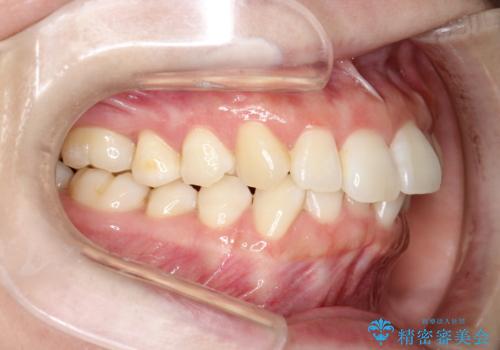

インビザライン ライトパッケージによる部分矯正治療 下の前歯のみの歯並び改善

- インビザライン ライトパッケージパーシャル(下顎のみ)

- 下の前歯の歯並びのみの改善をご希望されました。

インビザライン ライトパッケージ下顎のみ(1枚~14枚まで)での治療を行なっていきました。

マウスピース枚数 初回14枚 + 追加13枚

概ね7ヶ月で治療完了しました。

インビザラインのライトパッケージでは14枚までという枚数制限がありますが、限られた枚数の中で当院独自の工夫を随所に盛り込み、狙い通りの治療結果が得られました。